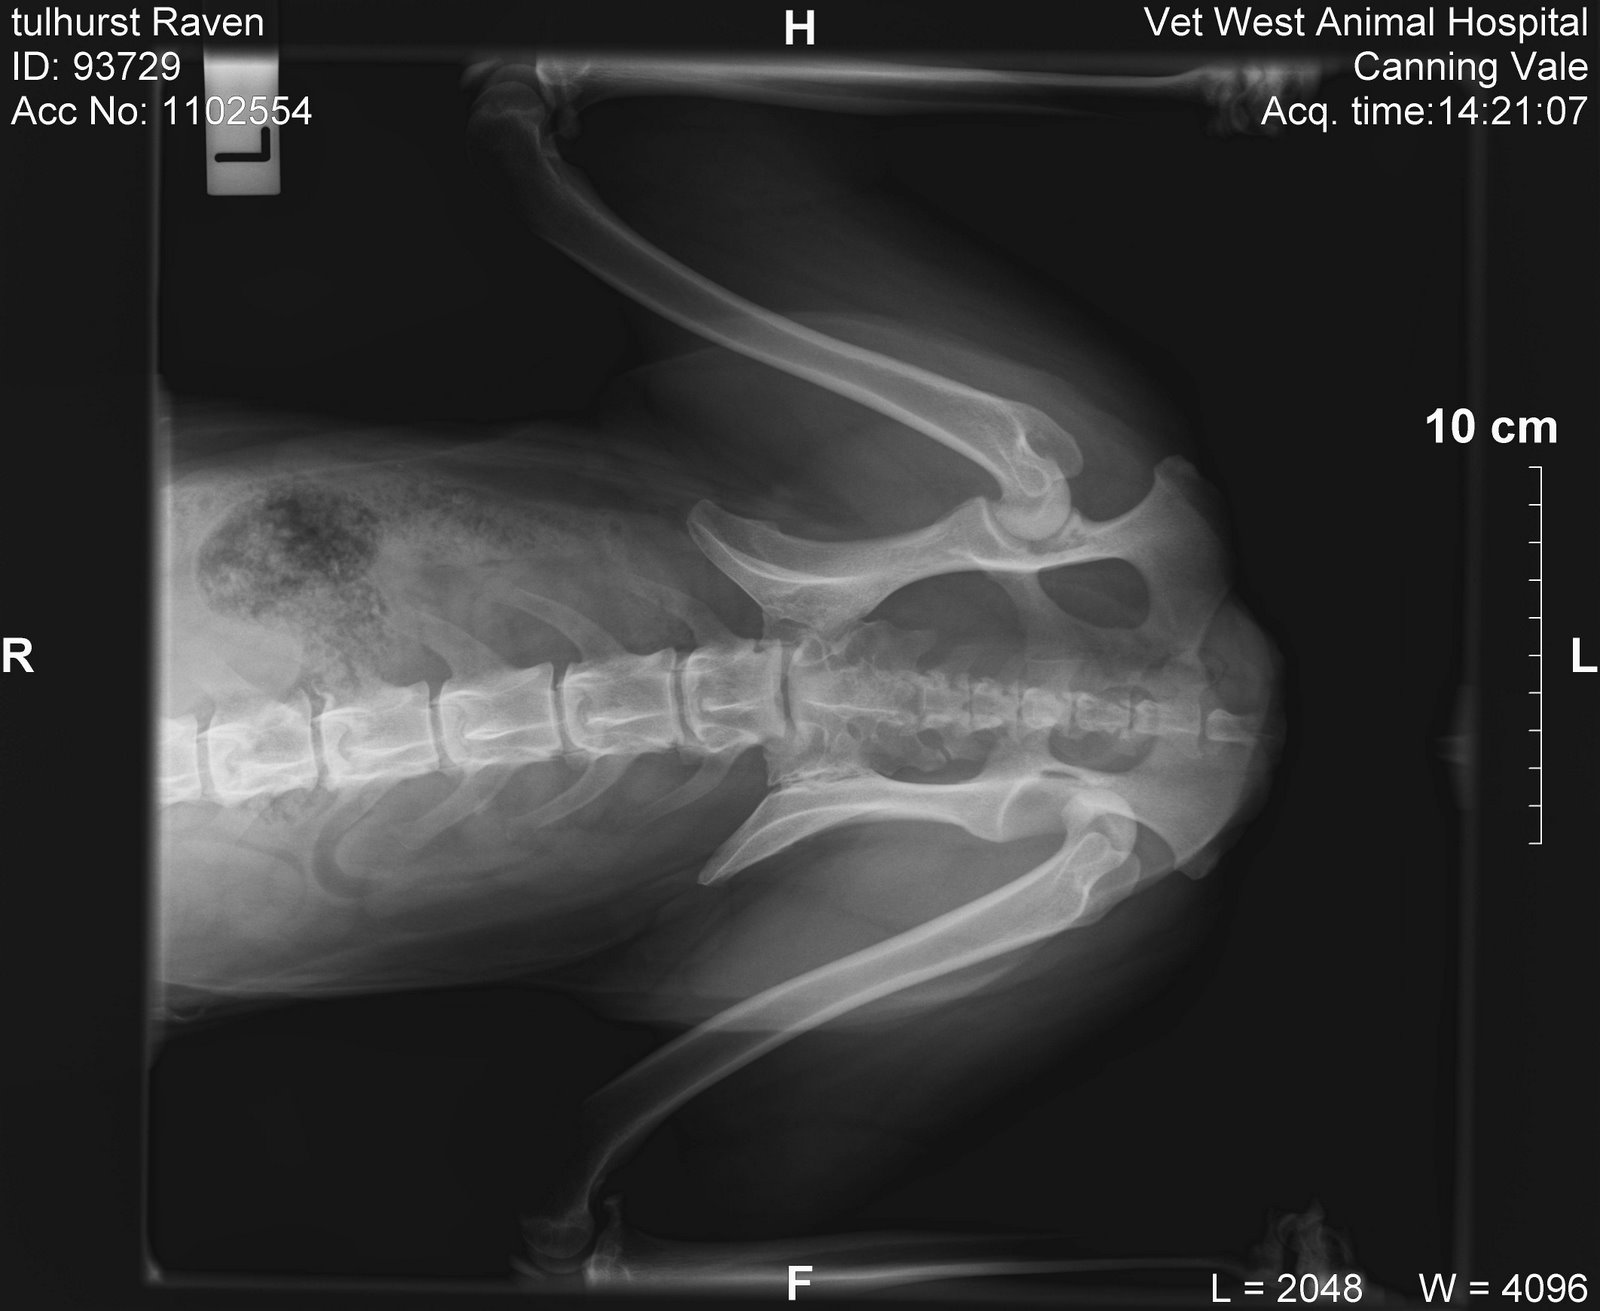

They would call me as soon as they knew what was what. So I get a call around 2.15 explaining that all has gone well, Raven is awake from the GA, they x-rayed and it was a dislocated hip and it was put back in without too much trouble, can I come pick her up at 5.15. Of course I asked if it could be any earlier but that was a no go. So I was there at 5.15 on the dot and saw the vet who had treated Raven. She took me through and showed me the x rays. I have included them below, the last image is obviously after the hip has been replaced. The vet informed me that this was a rather unusual dislocation as rather than up and above the pelvis the ball had been pushed down out of the socket.

Typical Raven always does things her own way! So we looked at the x rays and she told me that it went back in easily and didn’t cause any problems with popping back out. This is the risk apparently with dislocated hips. That they can pop back out at any time during recovery period. Usually the dogs are strapped to the point that it can’t physically pop out (so they are on three legs) and everyone holds their breath at the end of the two weeks when the strapping comes off but because Raven’s was different she has all four legs on the ground and is weight bearing. Right now completely normally weight bearing I might add. The dog wants to trot everywhere and the hobbles don’t stop her from doing that! She can still cock that leg on that hip when she wants to pee as well! So I am going to try and get a referral to an Ortho specialist and try and confirm whether this strapping is doing the job or if it needs modifying. Also to enquire about her recovery therapy and what I can do to make sure it’s the best she can get. It’s a little different when you are talking about a sports performance dog as compared to your average pet dog I think. Long story not so short I don’t know at this stage if she will be going to the Nationals. Looking at her right now I feel 70% confident that she will be sound by then but you just never know. I will not be making any decisions at this stage. So that was my drama for the weekend. And now Raven is bored out of her skull and wondering what all the fuss is about. Below is one of the xray images they took.